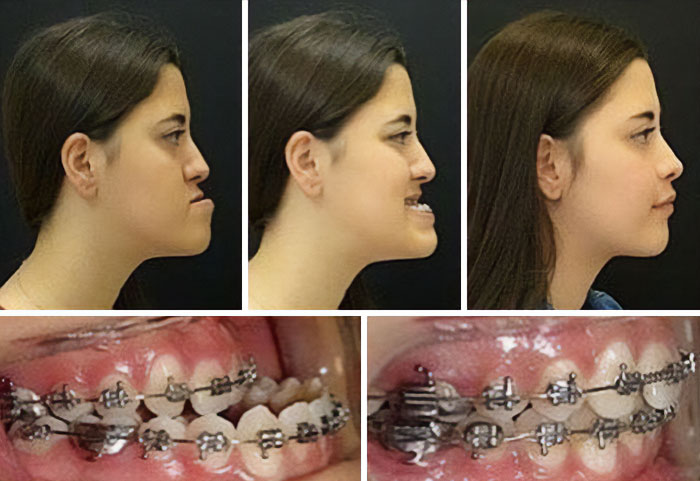

This Is How Great Surgery Has Evolved! Here You Can See The Result Of An Underbite Surgery And Jaw Positioning Correction